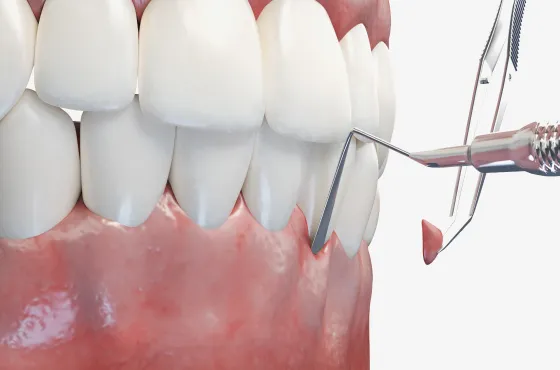

お口の中の様子を記録するためにデジタル写真を撮影します。拡大して見ることが可能なため、補綴物の適合性のチェック・虫歯のチェックなどに用います。

また、根本的な治療のために、主訴部位だけでなく口腔内全体の状態を把握する必要があります。そのために当院では口腔内全体のデジタルレントゲン撮影を行います。 -

02原因を徹底的に除去

原因除去療法には患者さまが行うものと医療者サイドが行うものが あります。まず、患者さまは、ブラッシング技術を向上させ、それを習慣化することが大切です。そして医療者サイドが行う原因除去療法とは、患者さまが歯を磨きやすい状態に整えることです。そのためには“被せる”、“詰める”などの精度を高めること。より天然歯に近い形体を実現することにより、磨きやすい状態が整えられます。また、治療により歯周ポケットをなくしたり、歯磨きに負けない強い歯肉をつくることも大切です。